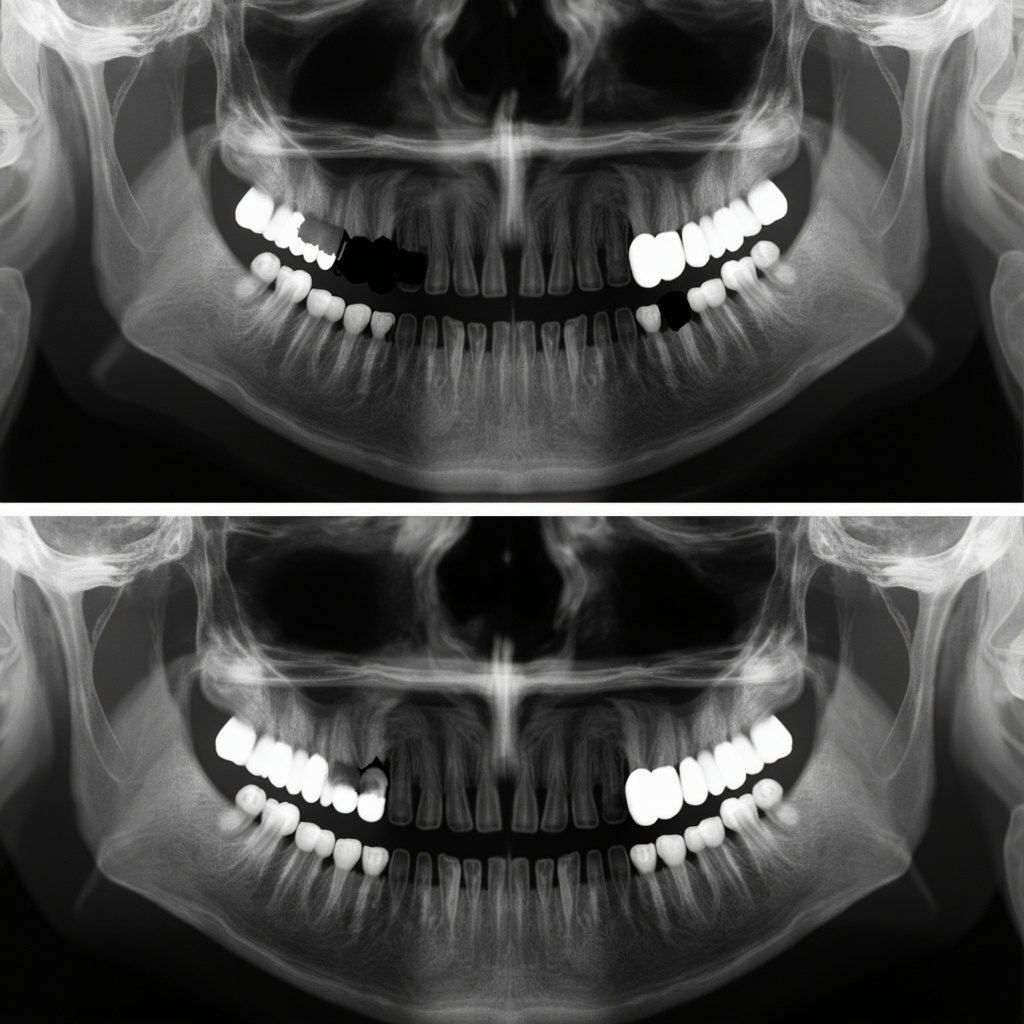

Dead pixels appear as consistently black spots in X-ray images. These pixels fail to respond to X-ray exposure and remain at zero signal regardless of the radiation intensity. Hot pixels manifest as consistently white or bright spots, remaining at maximum signal output even without X-ray exposure.

- Number of defective pixels: More than 5-10 defects typically warrant replacement

- Location of defects: Central defects impact diagnosis more than edge defects

Dead pixels and hot pixels in digital X-ray sensors are inevitable challenges in modern dental imaging. However, with proper understanding, regular monitoring, and appropriate maintenance protocols, their impact on diagnostic quality can be minimized. When pixel defects do occur, a combination of software corrections and professional repair services can often restore sensor functionality. Regular quality assurance testing remains the cornerstone of early detection and effective management of pixel defects in dental X-ray systems.